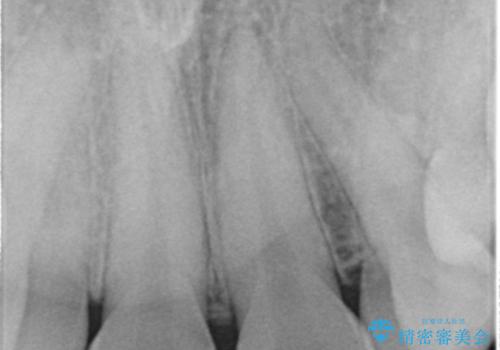

- 生まれつき上の側切歯と犬歯が逆に生えていることを主訴に来院された患者様です。

矯正以外の治療法で早く治したいとのご希望により、上顎両側犬歯を抜去しオールセラミックのブリッジによる補綴治療を行いました。